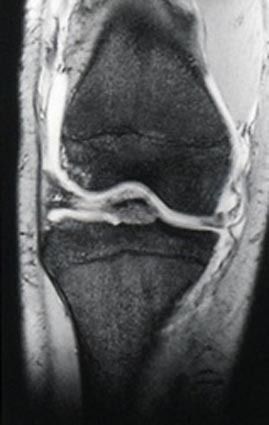

スキーで膝を捻ったり、タックルを受けて、膝が外反(内側に強く曲がる)すると膝の内側にある内側側副靭帯(以下MCL)を損傷することがあります。膝の靭帯損傷では比較的多い部位です。痛みは膝の内側にあり、膝をX脚になるようにストレスをかけると痛...